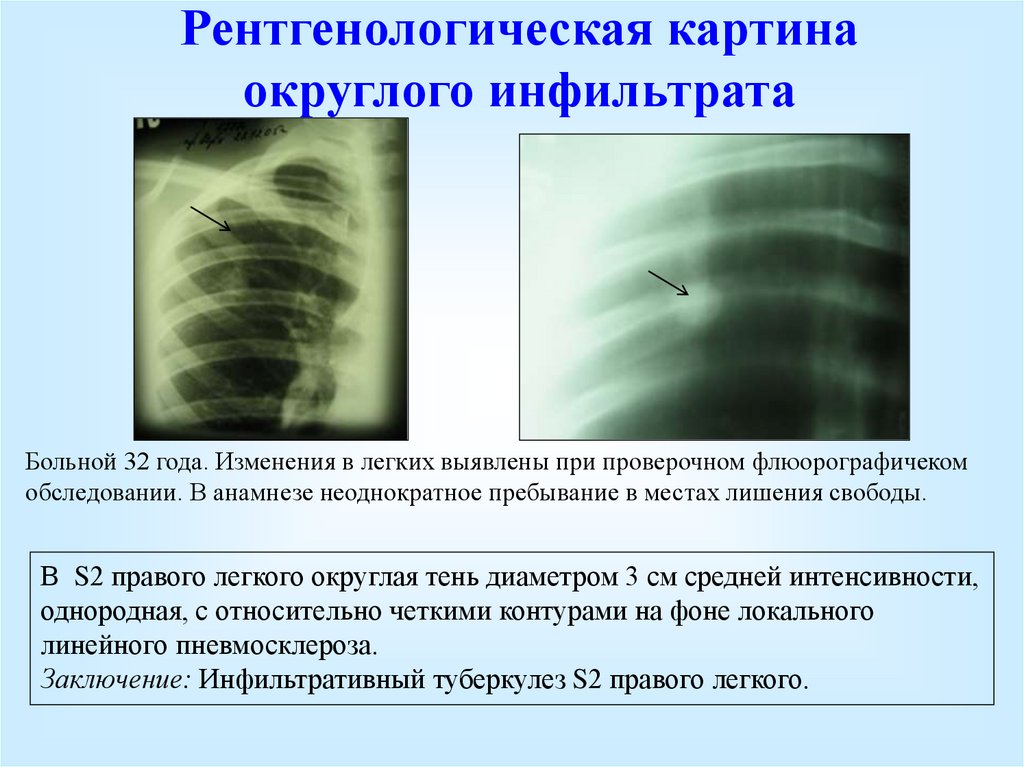

Очаговый и инфильтративный туберкулез презентация - 94 фото